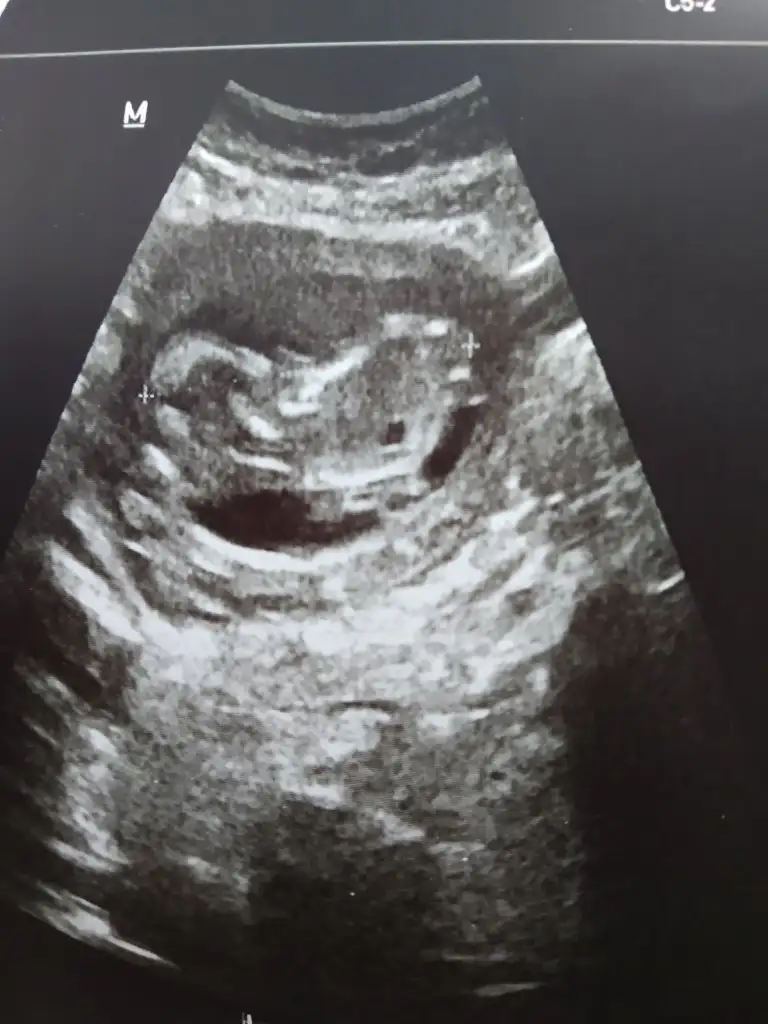

Ikra meyra Ikra meyra 13+3 cinsiyet tahmini yapabilir misin ultrosonda 12+5 çıktı

Eklentiler

• IMG_20210430_093326.webp

IMG_20210430_093326.webp

28,9 KB · Görüntüleme: 67

Kontrolden döndüm çok şükür güzel geçti herşey yolunda dedi doktor cinsiyeti belli olmadı iki hafta sonra yine bakarız dedi. 5 gün geride çıktı sadece 12+5 göründü ultrosonda 13+3 olmuştuk bugün olabilir normal dedi onada hareketliydi maşallah 😍😍🥰